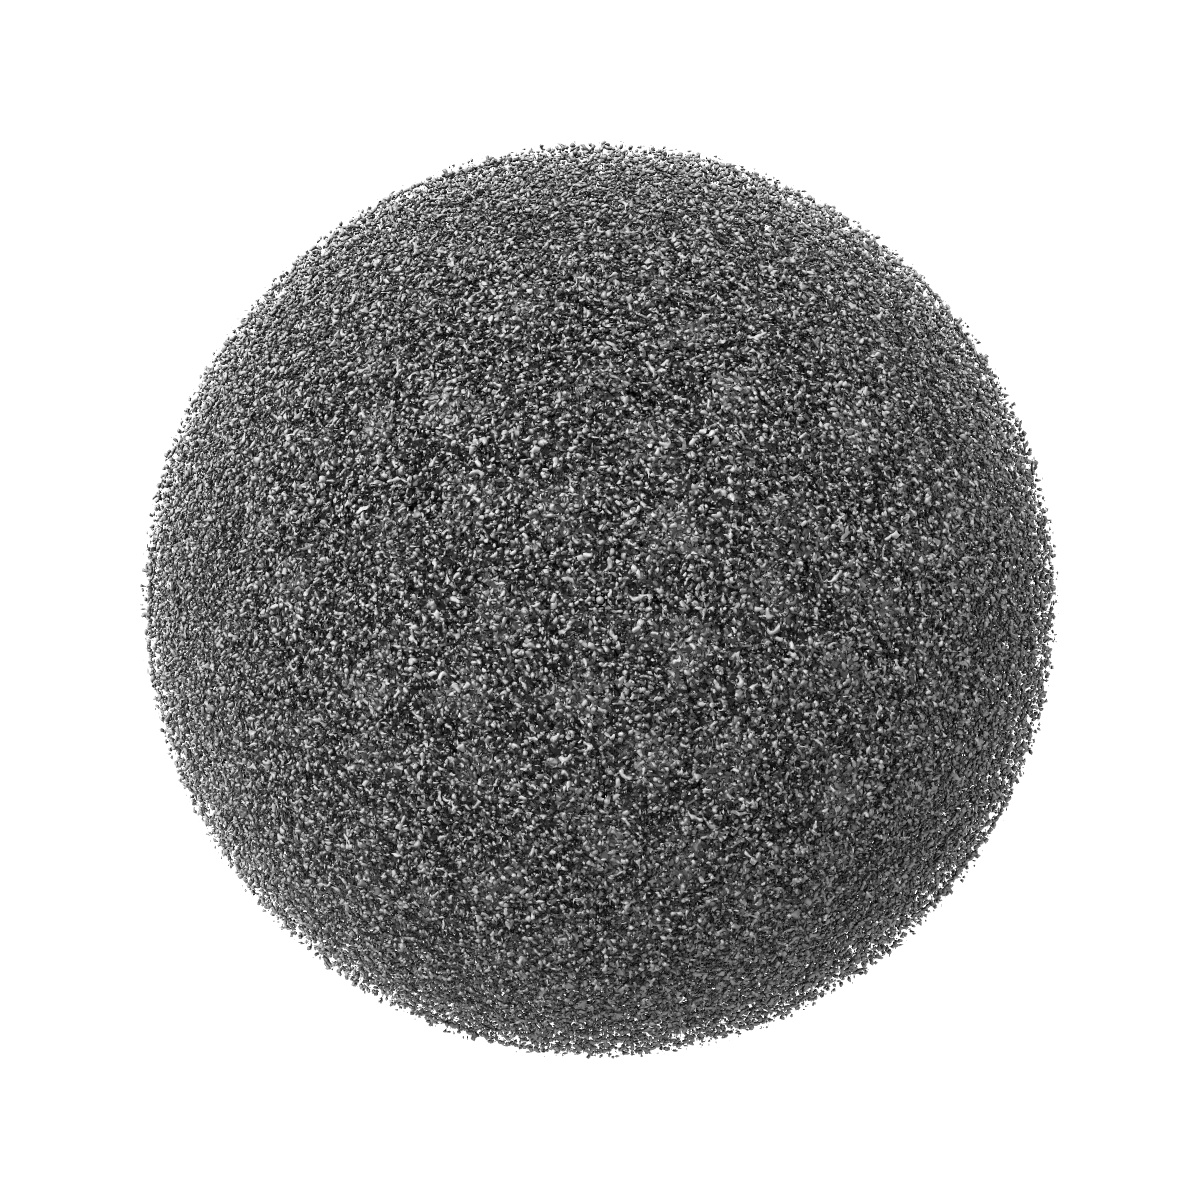

Cryo-EM structure of Dengue virus serotype 2 in complex with antigen-binding fragments of human antibody 2D22

Single-particle6.5 Å

Sample: Dengue virus serotype 2 strain PVP94/07 (a clinical isolate) complexed with Fab fragments of human antibody 2D22.

DENGUE VIRUS. Cryo-EM structure of an antibody that neutralizes dengue virus type 2 by locking E protein dimers.